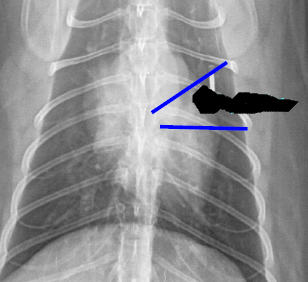

Mass on right side

Arteries up and away

Veins ventral and central